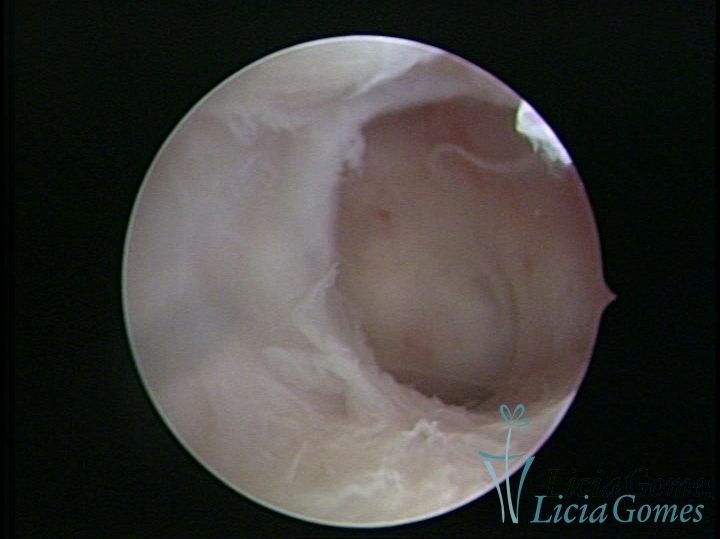

• SINÉQUIA TIPO FIBROSA